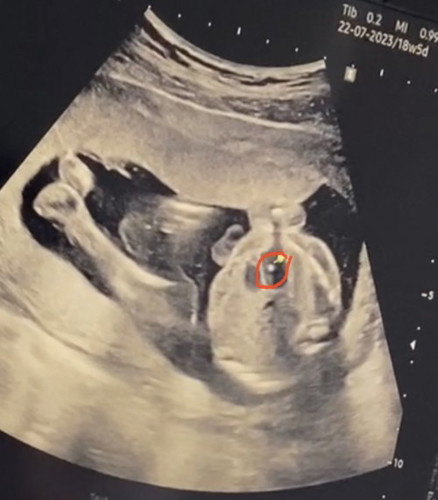

เจอก้อนแคลเซียมที่หัวใจลูก

มีคุณแม่ท่านใดเคยเจอมั้ยคะ ตอนนี้19wค่ะ ตรวจนิฟตอน10w ผลออกมาปกติค่ะ แต่กังวลว่าจะผลอะไรมั้ยคะ

ตรวจเจอเหมือนกันค่ะ รอให้อาจารย์หมอตรวจซ้ำอีกรอบค่ะ ตอนนี้ 20w ค่ะ

ท้องแรกหมอก็ตรวจเจอค่ะแต่โชคดีพอครรภ์แก่หายไปเองค่ะ